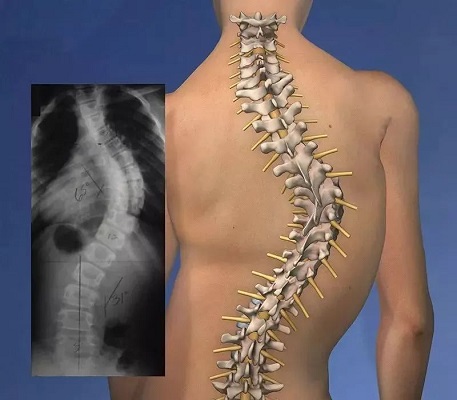

脊柱側彎,是脊柱的一個節段或者數個節段向側方發生了完全,同時還會伴有椎體旋轉的脊柱畸形疾病。一般拍攝X片,顯示脊柱有大于10度以上的側向彎曲,即可被診斷為脊柱側彎。而青少年脊柱側彎,則是患者在青少年時期發病的脊柱側彎,且由于青少年時期骨骼發育較迅速,出現脊柱側彎后,畸形發展會很迅速。